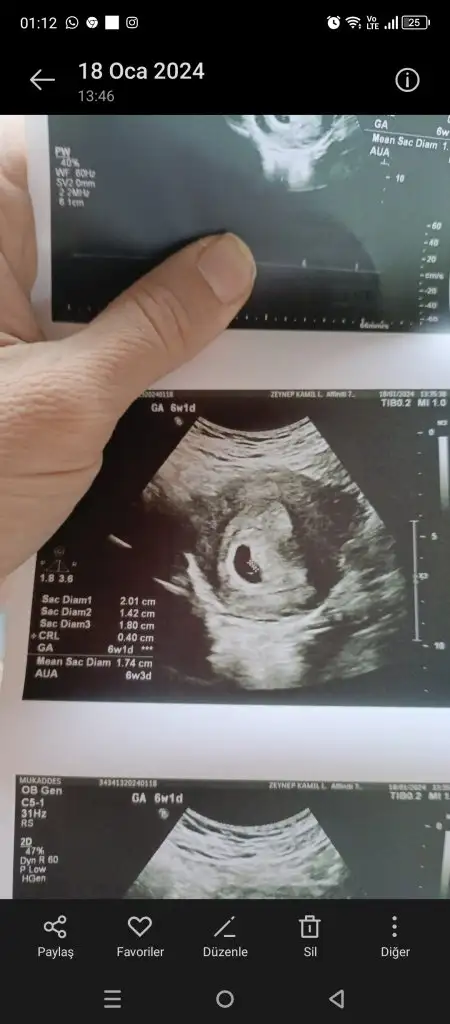

Evet benimkine bak yukarıda var resmîKeseler mi farkli anlamadim

Simdi gordum bakalim hayirlisiEvet benimkine bak yukarıda var resmî

Plesanta sağ da erkek canımmerhabalar ilk bebişimiz merakla bekliyoruz6. haftanın içindeyken gitmiştik,karından ultrason tahmininizi çok merak ediyorum

Eki Görüntüle 3398806